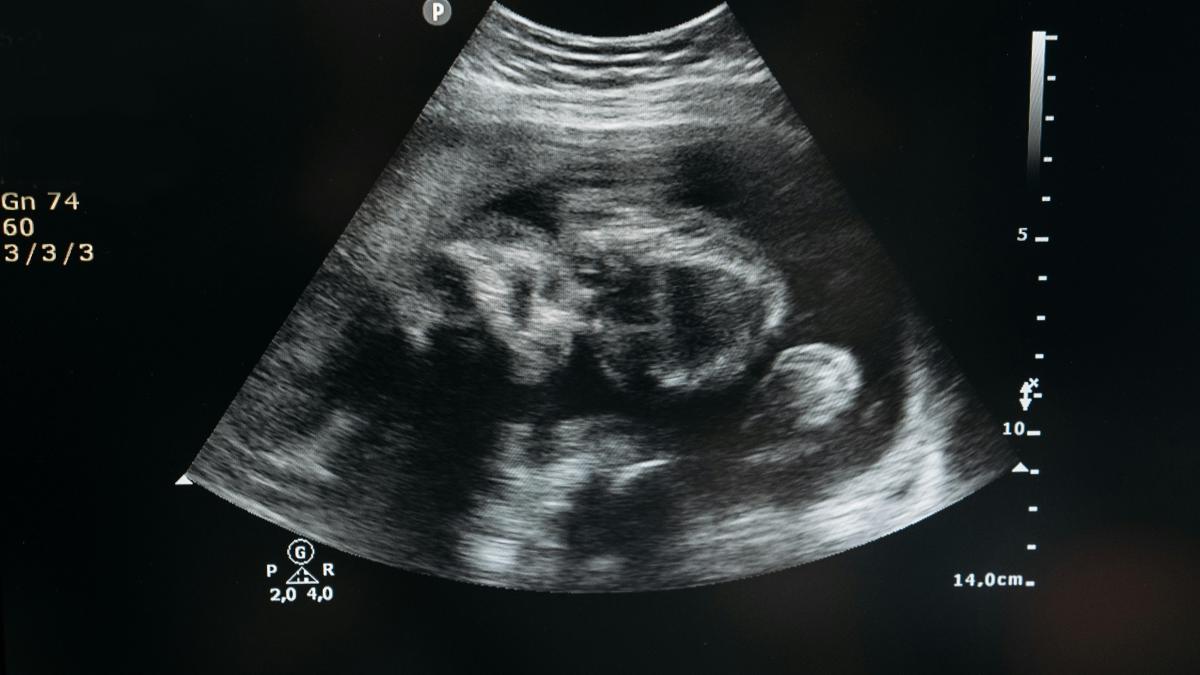

Un fenomen extrem de rar în obstetrică, lithopedionul sau „bebelușul de piatră” reprezintă calcificarea unui făt decedat care rămâne în organismul mamei, fără a fi eliminat.

Această condiție apare în urma unei sarcini ectopice abdominale, atunci când fătul moare, dar este prea mare pentru a fi reabsorbit de corpul mamei. Pentru a preveni infecțiile, organismul mamei învelește fătul într-un strat de calciu, transformându-l într-o masă solidă asemănătoare pietrei.

Lithopedionul se formează atunci când un făt moare în urma unei sarcini ectopice abdominale și este prea mare pentru a fi reabsorbit de corpul mamei. În loc să fie eliminat, fătul este învelit într-un strat de calciu, protejând astfel organismul mamei de infecții. Această calcifiere poate dura zeci de ani, iar femeile afectate pot rămâne asimptomatice sau pot prezenta simptome minore.